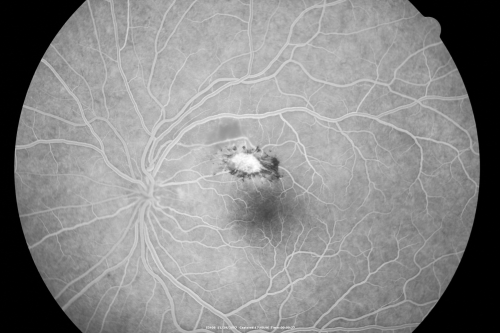

Toxoplasmosis - Inner Retinal - Recurrent - Treated with Bactrim DS

43-year-old man has macular toxoplasmosis. He has responded nicely to Bactrim OS: 20/60